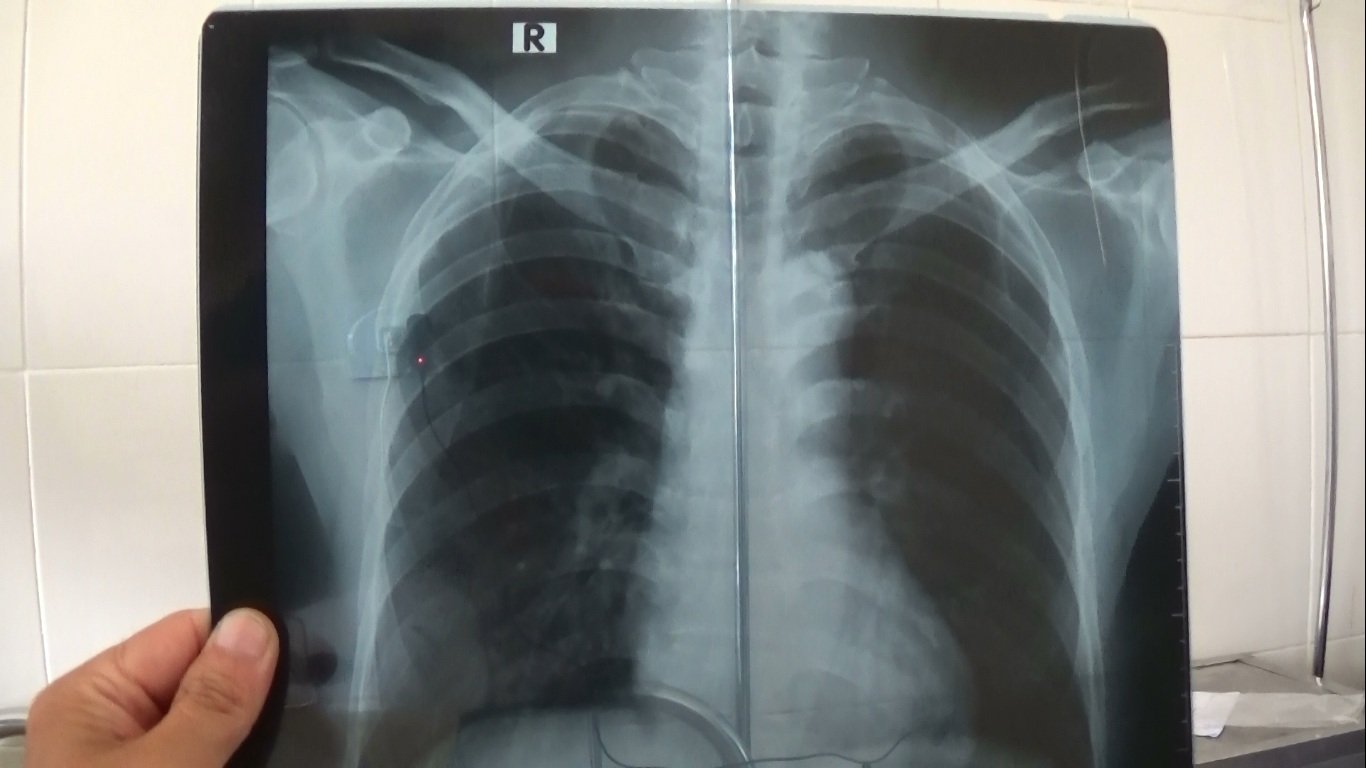

- Hưng Yên bị đánh gãy sườn